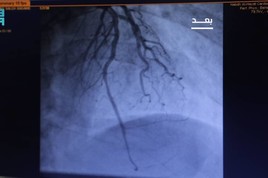

معالجین کا کہنا ہے کہ مصری زائر کے  مختلف ایکسرے لیے گئے  اور مطلوبہ ٹیسٹ کرائے گئے جن سے پتہ چلا کہ ان کے دل کے عضلات میں مسئلہ ہے اور پھیپھڑوں میں شدید سوزش ہے۔ مریض کو مصنوعی تنفس فراہم کیا گیا۔ ان کو انتہائی نگہداشت کے داخل کیا گیا۔ صحت میں بہتری آنے تک ایمرجنسی وارڈ میں رکھا گیا۔